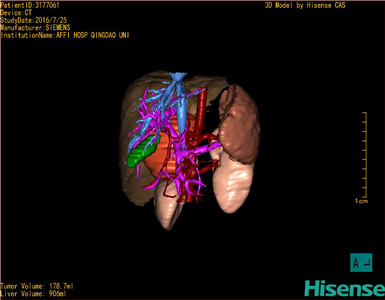

将0.625mm双源薄层CT资料的静脉期和动脉期Dicom格式文件导入海信CAS系统。

通过调节窗宽窗位调整CT序号,对肿瘤,肝实质,胆囊,下腔静脉,肿瘤,肝动脉、门静脉及肝静脉等进行三维重建;系统自动计算肿瘤体积和肝脏体积。

模拟手术操作,自动计算切除肿瘤体积。肝脏体积为906ml,肿瘤体积为178.7ml,肿瘤体积为肝脏体积的19.7%,通过比对6-9月正常肝脏体积为257.75±51.05ml,通过术前模拟手术,精准判断切除后剩余肝脏体积能耐受,避免肝衰竭发生。

术前三维重建:

重建图片